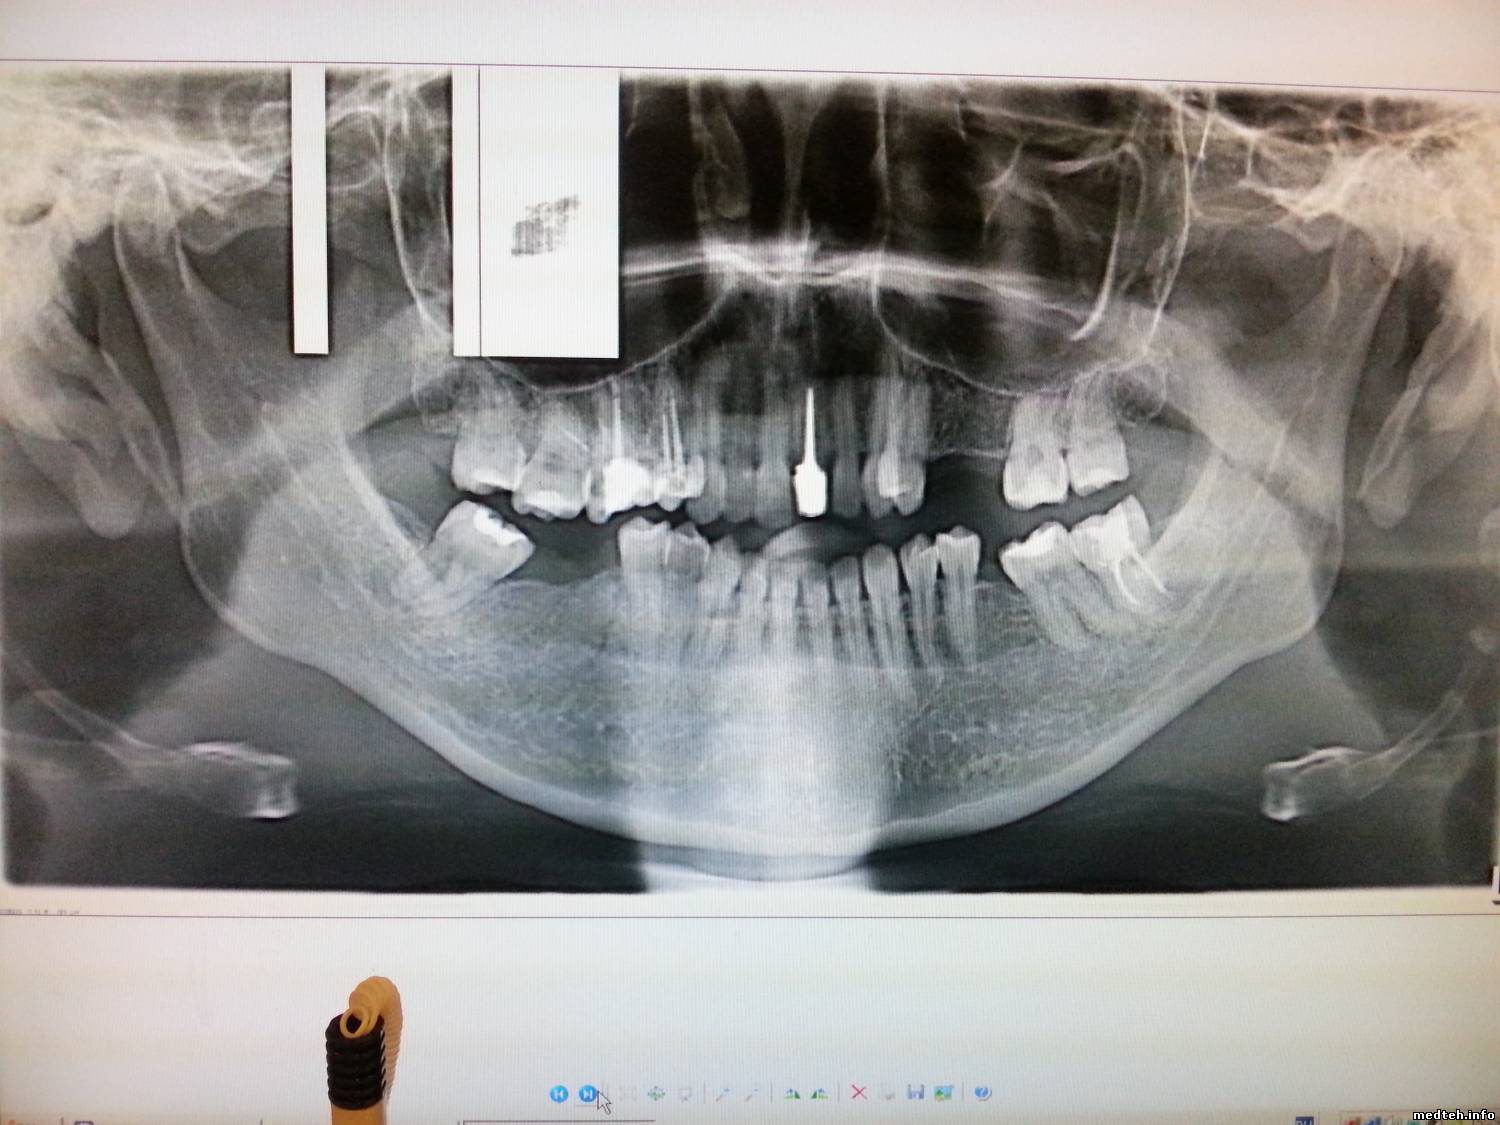

Стали возникать вырывы в верхней трети изображения (периодически), также присутствуют моменты расфокусировки и пропадания изображения в середине нижней части снимка.

4430131.jpg (159.4 Kb) · 2981457.jpg (153.2 Kb) · 8950514.jpg (149.7 Kb)

Нижняя часть снимка: - передник с воротником + неправильное позиционирование(второй снимок).

Передник тут ни причём. "Воротник" появляется периодически без всякой системы, таких снимков за год набралось около сотни.

Похоже после ухода за ширму рентгенлаборанта пациент расслабляется и втягивает голову (снимки №1 и 3).

Датчик болтается (болезнь Sirona) + неправильное позиционирование.

МастерБаку предложил дельную мысль, попробую обязательно, но также беспокоит дефект верхней части снимка ireful $IMAGE3$$IMAGE1$$IMAGE2$ Это к вопросу о модели аппарата. Всем.

Неровные края сверху и снизу - это огрехи сборки. Даже думаю, что на заводе.